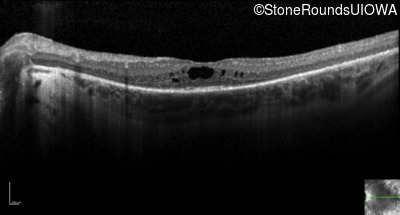

Optical Coherence Tomography - Right - 20/60 -1

Exemplar / OCT Stack